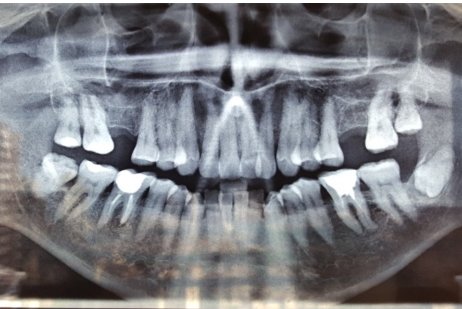

Мне 15 лет. Сегодня начал болеть двадцать восьмой зуб. Болит при надавливании или просто при закрывании рта очень сильно и существует чувство "выросшего" зуба. На нем имеются две маленькие дырочки, еле заметные. Опухла десна возле этого зуба, она также болит при надавливании.

Я вам уже отвечал на ваш вопрос. Невозможно точно определить причину ваших беспокойств. Вам необходимо срочно обратиться к стоматологу, оценить необходимости лечения, либо удаления данного зуба. Несколько раз в день, старайтесь полоскать раствором соль, сода и 4 - 5 капель йода на стакан воды.